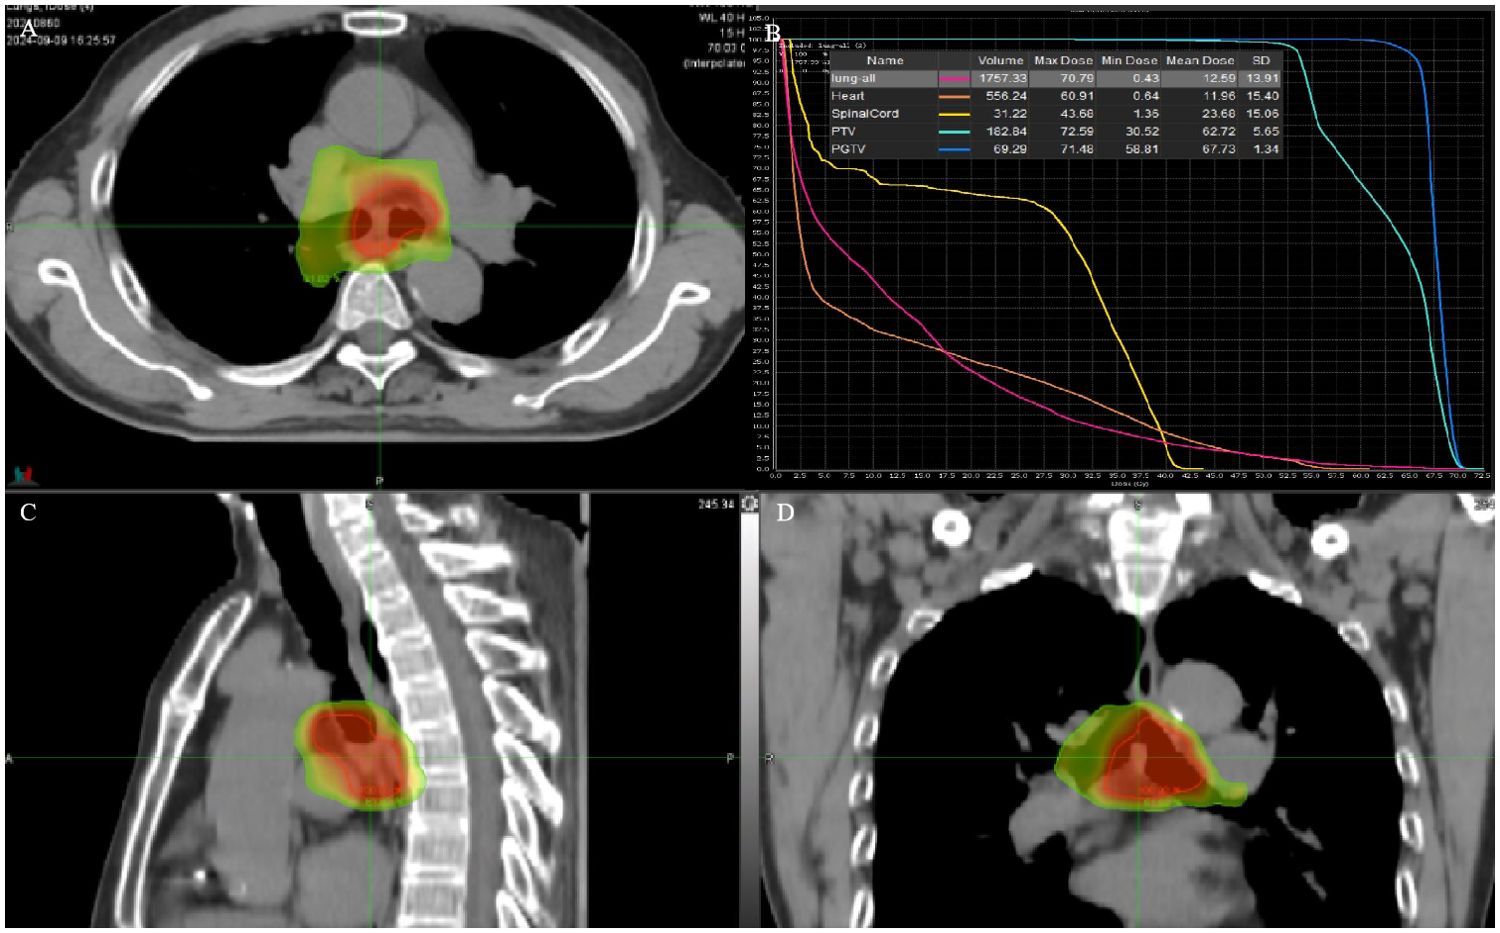

The patient refused an operation due to his advanced age. He received intensity-modulated conformal radiation therapy (IMRT) of TOMOtherapy (USA), the target volume of which was described as follows: according to contrast-enhanced CT and PET/CT images to delineate the target, the gross tumor volume (GTV) comprised a gross tumor, the clinical target volume (CTV) had an area of 2 cm above and below the tumor, and CTV was enlarged 5 mm circumferentially to form the planning target volume (PTV). GTV was also enlarged 5 mm circumferentially to form the PGTV. The dose of PGTV was 66 Gy in 33 fractions of 2 Gy, while that of PTV was 54 Gy/30f (Figures 2A–D).

Figure 2. (A, C, D) RT target; area of red line: 66 Gy; and area of yellow line: 54 Gy. (B) DVH of case 1 patient.